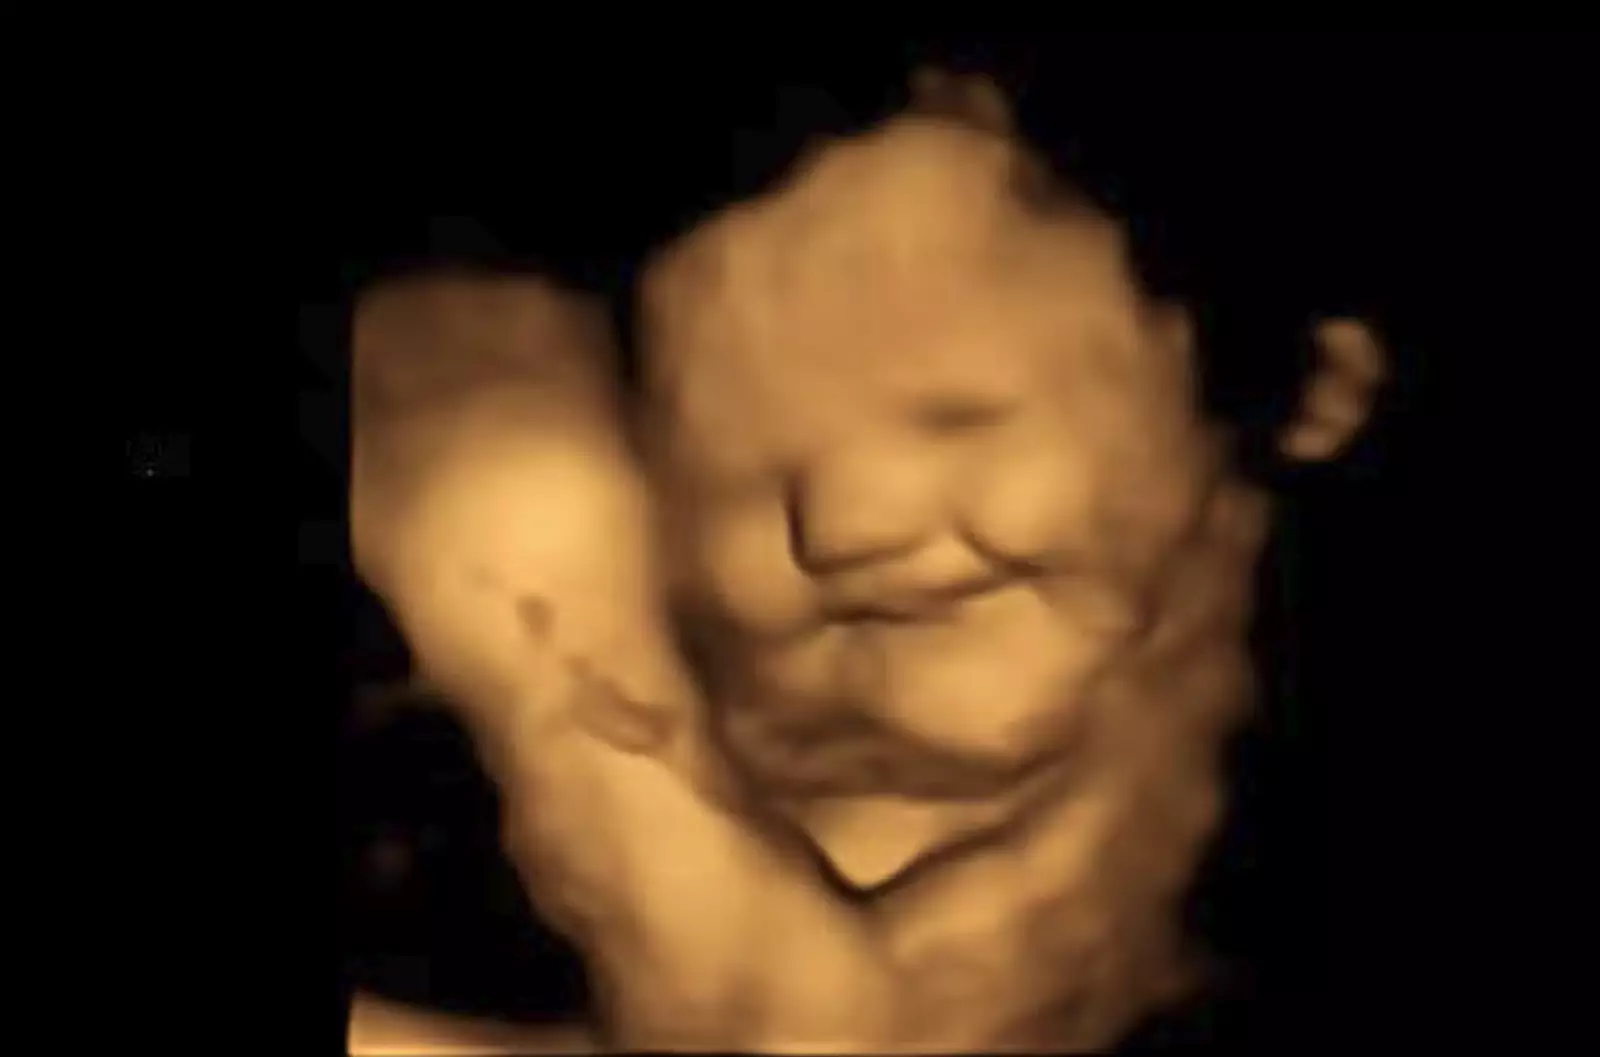

Исследователи из Даремского университета провели 4D-ультразвуковое сканирование беременных женщин, чтобы увидеть, как нерожденные дети гримасничали от разных продуктов, которые ели их матери.

Группа привлекла 100 беременных женщин в возрасте от 18 до 40 лет и провела 4D-УЗИ на 32-й и 36-й неделе беременности. Женщинам давали одну капсулу за 20 минут до сканирования, содержащую либо 400 мг моркови, либо 400 мг порошка капусты.

Результаты показали, что зародыши улыбались вскоре после того, как их матери съели морковь, однако кривились, когда мамы выбирали капусту кале. Даже небольшого количества моркови или капусты было достаточно, чтобы вызвать реакцию у плода.